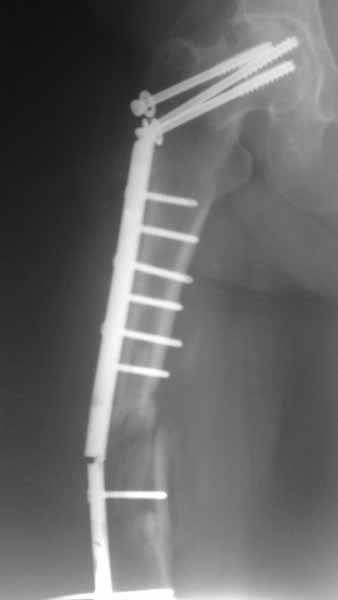

Псевдоартроз бедра

Оперирована 12 месяцев назад в связи с медиальным переломом шейки бедренной кости и оскольчатым переломом диафиза бедренной кости. На то время в Украине не было систем БИОС, позволяющих фиксировать одновременно оба перелома, поэтому выполнена фиксация тем, чем могли. Около 1 мес назад больная начала передвигаться с тростью.Что в данном случае лучше сделать?